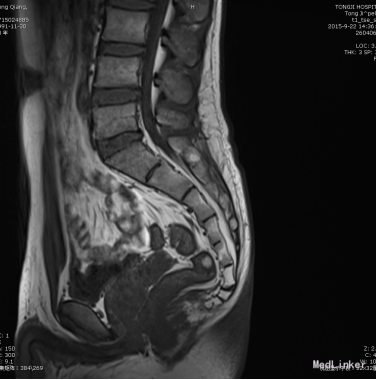

患者,男,23岁。 主诉:进行性排尿困难4年余。 现病史:患者4年前无明显诱因出现排尿困难,夜尿1次,间或有排尿不尽感。于当地医院抗感染治疗,症状未见明显好转。2015-9-21于我院行尿动力检查示:膀胱初感觉减退;膀胱收缩力弱+;残余尿134ml。2015-9-22于我院行腰骶丛MRI示:双侧S1、S2神经根处束膜囊肿,最大位于右侧S2神经根处,大小5*6mm。 既往史:既往体健,未诉异常。

查体:T: 36.5 ℃ P:64 次/分 R: 20 次/分 BP: 108/73 mmHg;双肾区无叩痛,输尿管走行区压痛(-),脊柱四肢活动正常,肛门外生殖器无异常。 辅助检查: 2015-9-21于我院行尿动力检查示:膀胱初感觉减退;膀胱收缩力弱+;残余尿134ml。2015-9-22于我院行腰骶丛MRI示:双侧S1、S2神经根处束膜囊肿,最大位于右侧S2神经根处,大小5*6mm。 尿液常规分析:红细胞(隐血) (±) ↑ 白细胞(粒) 2+ ↑ 红细胞计数 14.4 ↑ /ul 白细胞计数. 上皮细胞计数 18.5 ↑ /ul 495.00 ↑ /ul。